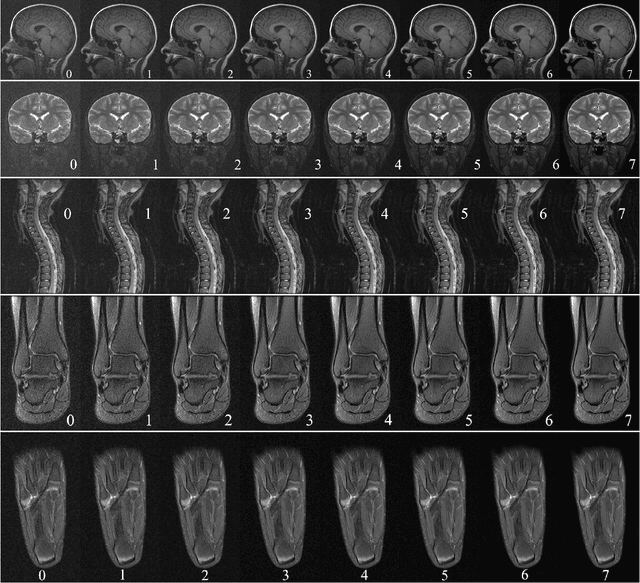

Abstract:Manual prescription of the field of view (FOV) by MRI technologists is variable and prolongs the scanning process. Often, the FOV is too large or crops critical anatomy. We propose a deep-learning framework, trained by radiologists' supervision, for automating FOV prescription. An intra-stack shared feature extraction network and an attention network are used to process a stack of 2D image inputs to generate output scalars defining the location of a rectangular region of interest (ROI). The attention mechanism is used to make the model focus on the small number of informative slices in a stack. Then the smallest FOV that makes the neural network predicted ROI free of aliasing is calculated by an algebraic operation derived from MR sampling theory. We retrospectively collected 595 cases between February 2018 and February 2022. The framework's performance is examined quantitatively with intersection over union (IoU) and pixel error on position, and qualitatively with a reader study. We use the t-test for comparing quantitative results from all models and a radiologist. The proposed model achieves an average IoU of 0.867 and average ROI position error of 9.06 out of 512 pixels on 80 test cases, significantly better (P<0.05) than two baseline models and not significantly different from a radiologist (P>0.12). Finally, the FOV given by the proposed framework achieves an acceptance rate of 92% from an experienced radiologist.